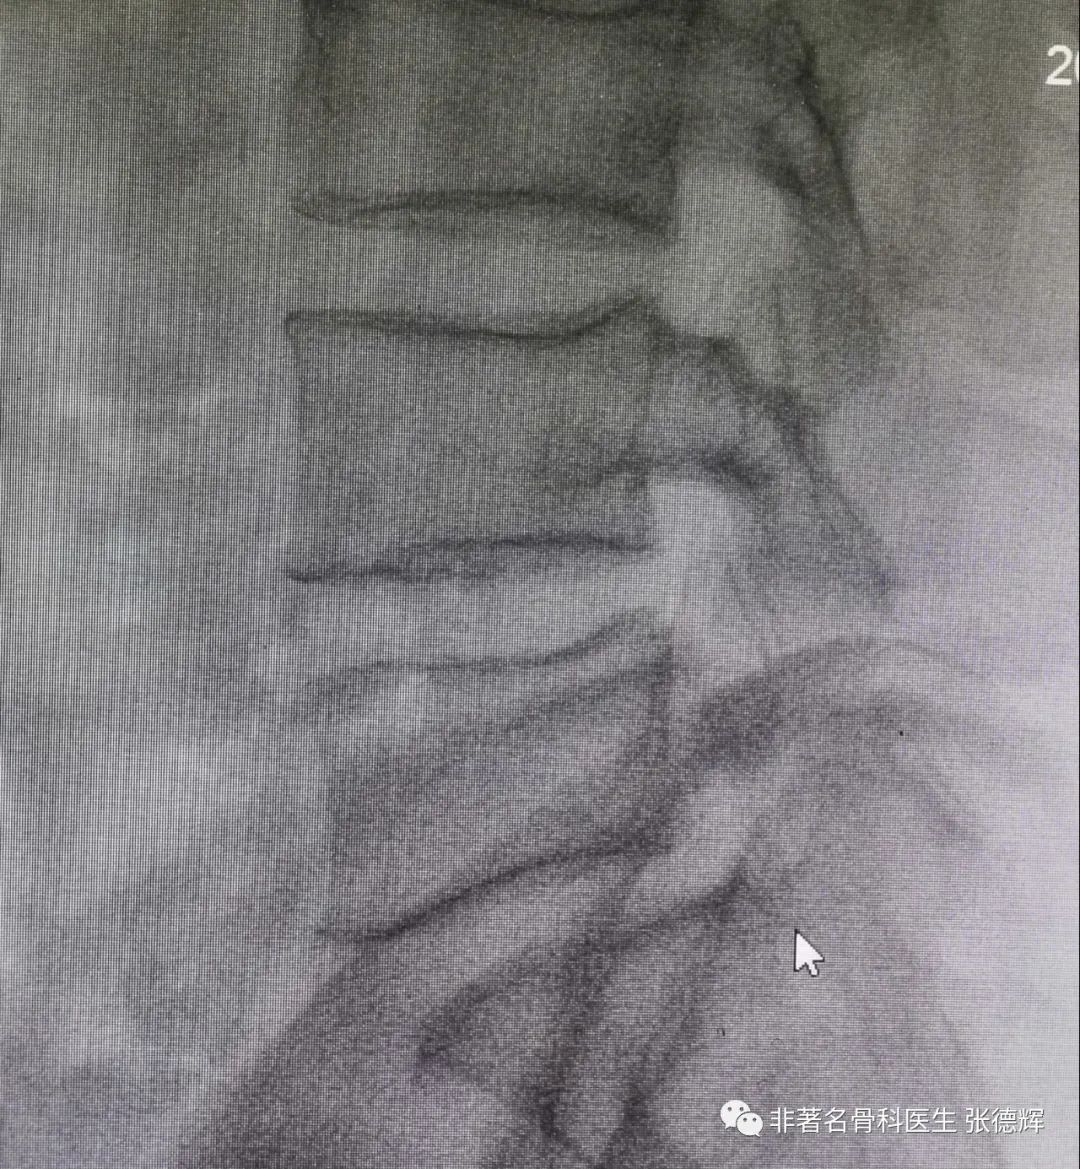

近期接诊一位腰椎峡部裂的患者,体重接近100公斤,腰腿痛近1年,严重时行走障碍,以下是影像检查资料。可以看到是明显的 腰5双侧峡部裂并轻度滑脱 。

腰椎侧位片可见腰5轻度向前滑移

腰椎双侧斜位片可见腰5双侧峡部骨质不连续

(“狗颈征”阳性,鼠标指示处)

腰椎动力位片(过伸过屈位片)可见腰5相对于骶1轻度滑移